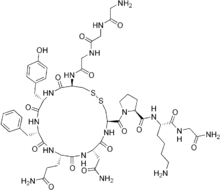

| Formula | C52H74N16O15S2 |

| Molar mass | 1227.38 g·mol−1 |